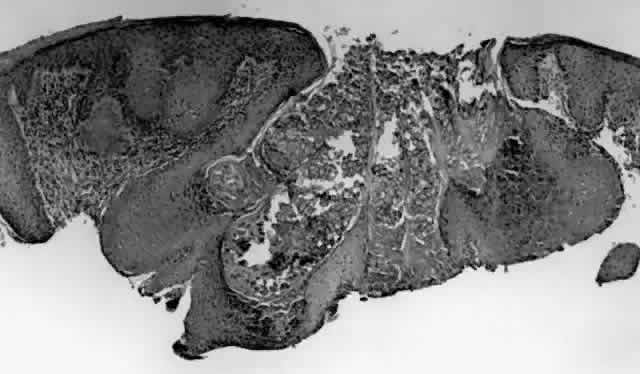

Fig. 4. Eyelid papilloma, histology. Low-power view of frond-like architecture with acanthotic epithelium with hyperkeratosis and fibrovascular cores. (Original magnification × 25)

HPV-induced conjunctival squamous papillomas demonstrate papillomatosis, acanthosis, and koilocytosis (Fig. 6). Because they are mucous membrane lesions, those of the conjunctiva and lacrimal sac show no granular cell layer but will show keratinization if they are large or exposed (Fig. 7). In our experience the frequency of koilocytes is variable, even in lesions almost certain to be viral (Fig. 8). Scattered inflammatory cells may be present in the cores or epithelium. Virus can be detected immunohistochemically in the nuclei of the cells (Fig. 9).

Fig. 6. Eyelid papilloma, histology. High-power view of acanthotic epithelium and koilocytes. (Original magnification × 400)

Squamous papillomas of the eyelid are exophytic lesions with multiple fronds, each showing acanthotic epithelium around a fibrovascular core. There is typically hyperkeratosis and koilocytosis. Inflammatory cells may be present.